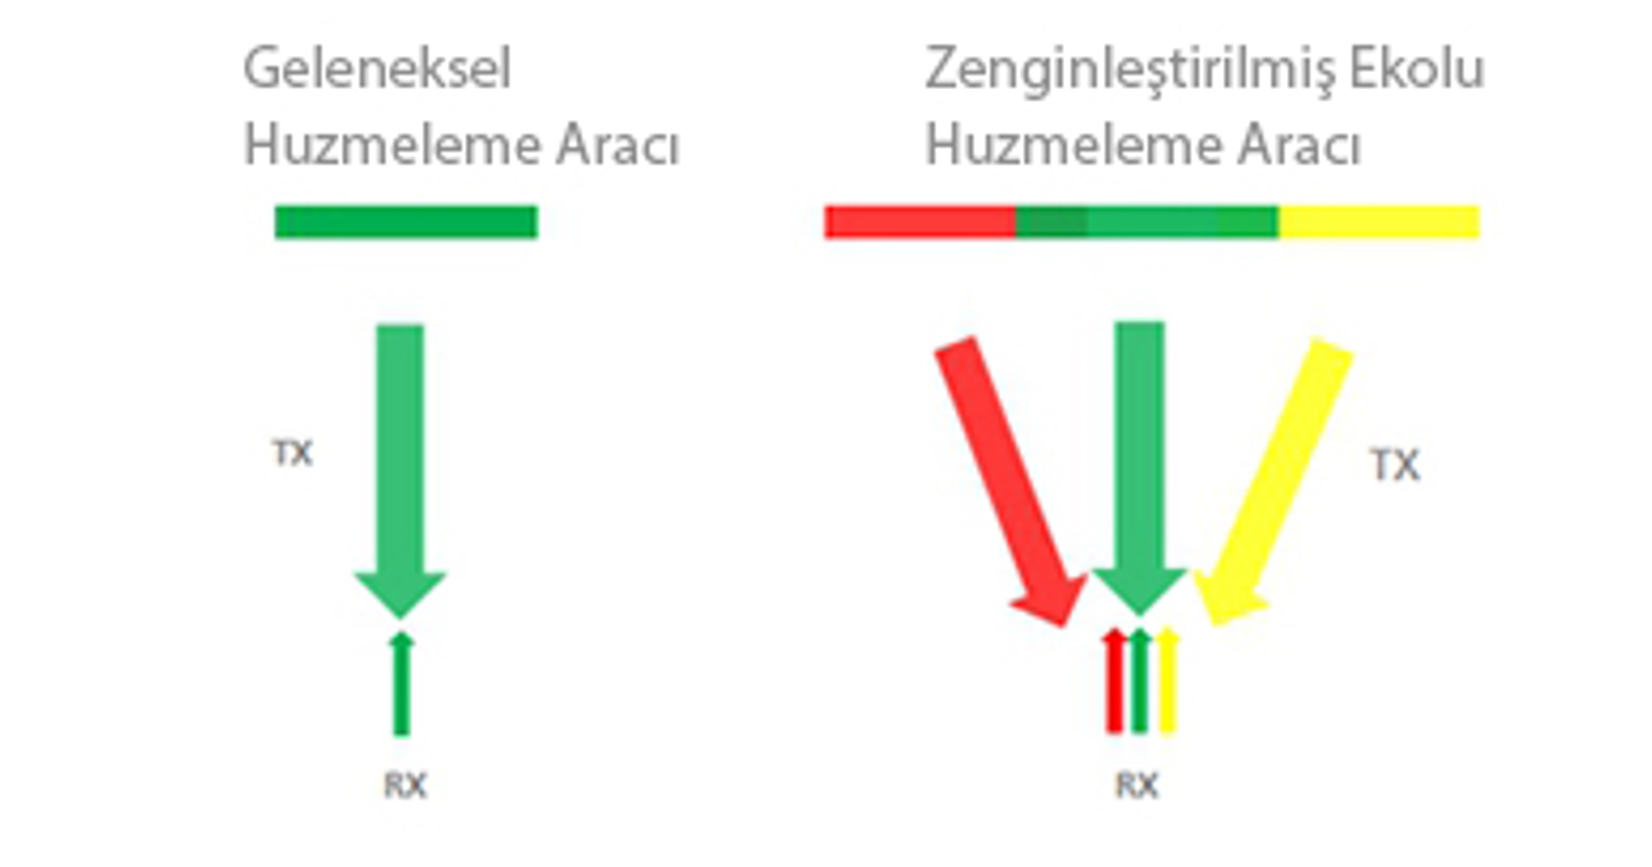

Zenginle?tirilmi? Ekolu I??n Olu?turma

Zenginle?tirilmi? ekolu ???n olu?turucu, tek bir daha ince ve daha gĂŒ?lĂŒ g?rĂŒntĂŒleme ???n? olu?turmak i?in geleneksel olarak g?z ard? edilmi? kom?u ???nlar?n eko sinyallerinin kullan?m?na izin verir, b?ylece daha iyi "hedef d???" g?rĂŒntĂŒ ??zĂŒnĂŒrlĂŒ?ĂŒ ve daha derin g?rĂŒntĂŒ penetrasyonu sa?lan?r.